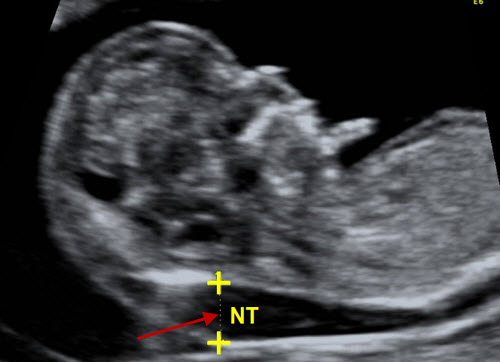

Độ mờ da gáy là gì ?

Độ trong của nuchal là chất lỏng được tìm thấy ở phía sau đầu và cổ bé của bạn, ngay bên dưới da. Độ dày của chất lỏng này có thể được đo chính xác và điều này được gọi là phép đo độ trong mờ (hay NT). Thông thường lượng chất lỏng nhỏ, tạo ra phép đo NT mỏng.

Chúng ta biết rằng lượng chất lỏng có thể tăng khi có một số điều kiện nhất định, tạo ra phép đo NT dày hơn. Các điều kiện liên quan đến phép đo NT tăng bao gồm một số bất thường nhiễm sắc thể (ví dụ, trisomy 13, 18 và 21) và một số vấn đề về cấu trúc (ví dụ, bất thường về tim). Đo NT tăng không phải lúc nào cũng có nghĩa là em bé có vấn đề nhưng nó làm tăng nguy cơ.

Có các tiêu chí được thiết lập và nghiêm ngặt để đo lường chính xác độ trong mờ của nuchal. Điều quan trọng là phép đo phải được thực hiện đúng để đảm bảo kết quả chính xác. Nếu em bé của bạn không hợp tác và NT không thể được đo chính xác, chúng tôi có thể yêu cầu bạn quay lại để có thêm hình ảnh sau đó trong ngày. Thỉnh thoảng, bệnh nhân cần quay lại vào một ngày khác nếu em bé vẫn ở trong tư thế không có ích.